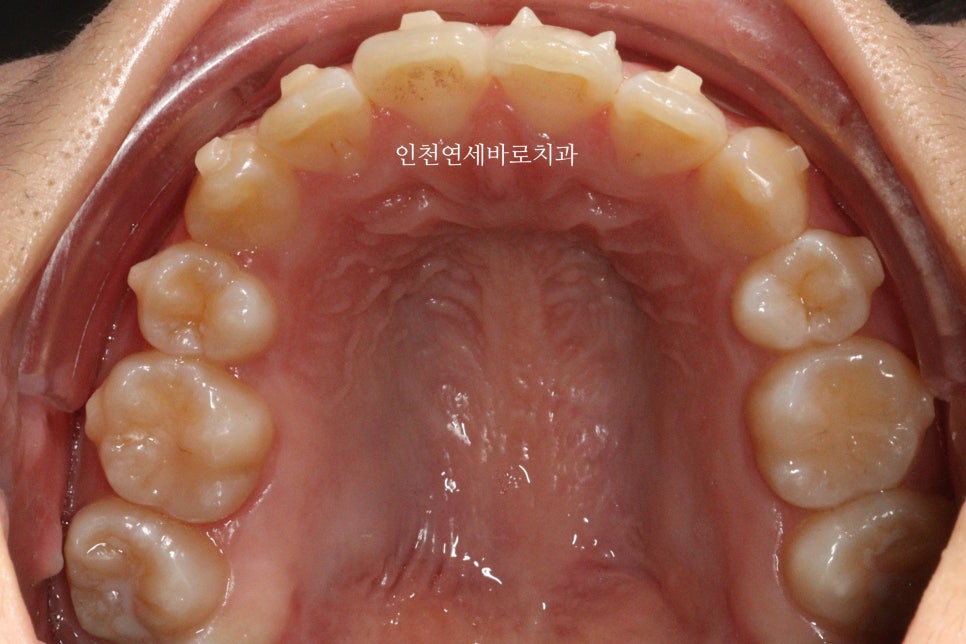

그리고 치료가 마무리 된 후의 모습입니다.

부분교정으로 앞니만 철사를 붙여서도 비슷한 효과를 볼 수 있었을지 모릅니다.

하지만 치아의 삭제가 많은 양 동반되지 않았다면 앞니가 분명 뻗쳐나왔을것입니다.

하지만 인비절라인은 전체교정에 준하는

치아와 주변조직에 무리가 되지 않는 범위에서의 확장을 만들어낼 수 있어

앞니의 뻗침을 최소화 할 수 있는 장점이 있습니다.

위 환자분의 재교정 치료기간은 약 7개월입니다.

7개월동안 병원은 두번 왔구요.